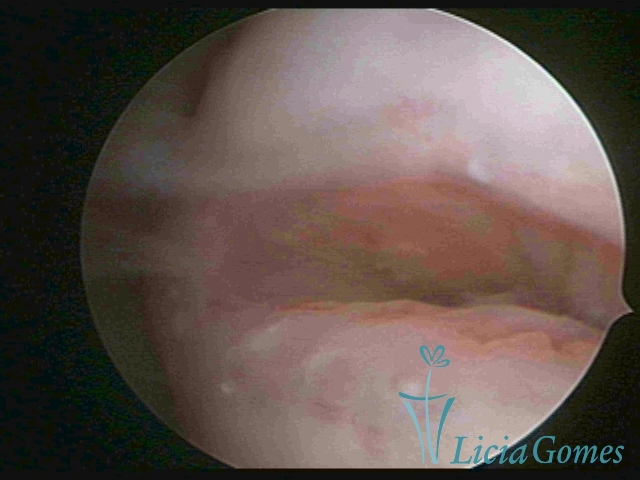

Second part or middle section

In the middle section of the cervical canal, the details of the buds are lost. It is possible to view creases and crypts. Longitudinal grooves are frequently observed. They are the most compact tissues presenting the most vascularized surface, whose vessels follow its passageway.